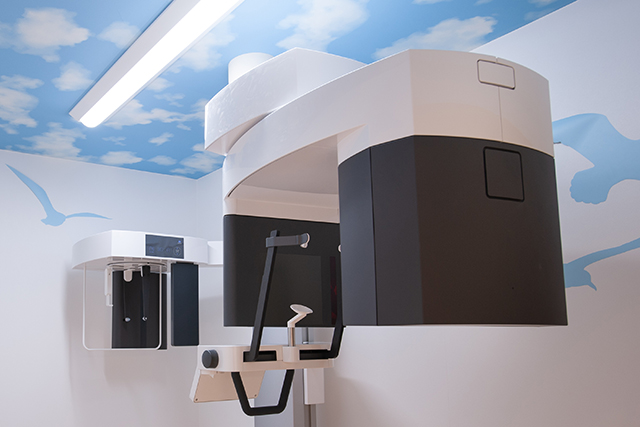

インプラント治療のための設備を用意

当院では、安心安全なインプラント治療の為の先端的な設備を整えています。院内にもCTを完備しております。

歯科用CT

インプラントの治療は、顎の骨に人工の歯根を埋め込みます。

事前にCTの撮影を行い、患者さまの骨の状態を精密に確認しておく必要があります。

当院は、歯科用CTを完備し、インプラント治療に必要となる骨の状態を精密に把握させていただいた後、治療計画を立案させていただいております。